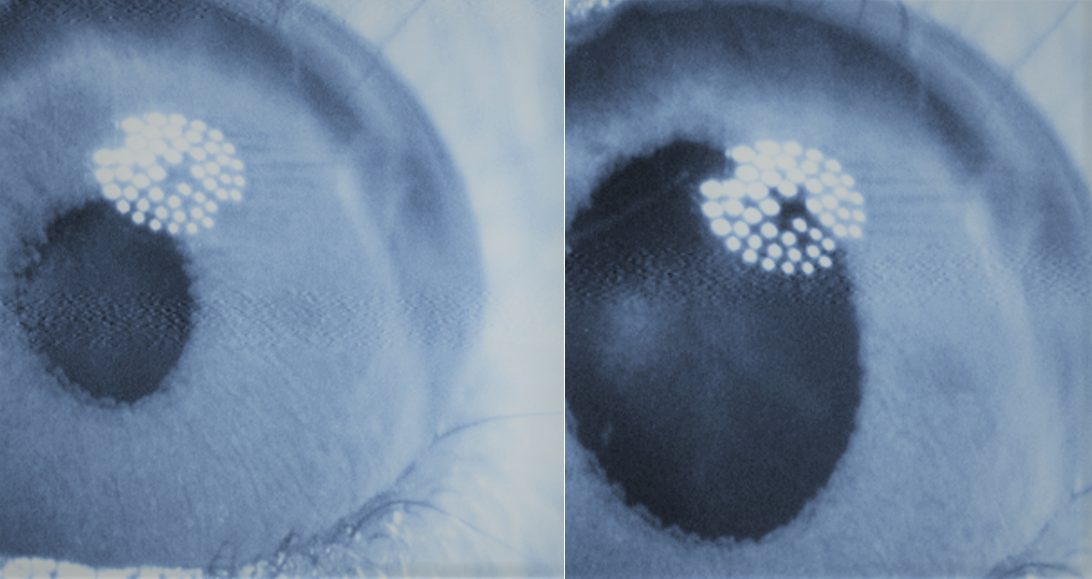

Construyen la primera retina artificial con biomaterial de seda para tratar una degeneración de la mácula